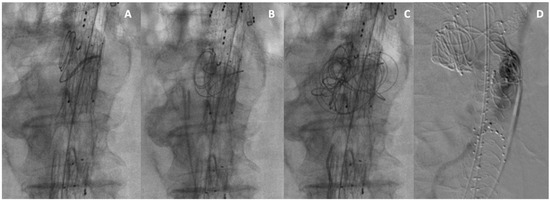

Embo F/BEVAR Case Descriptions and Preliminary Results